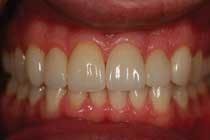

3. Esthetic enhancement and cementation — Once completed, the final restoration can then be either hand-polished or glazed chairside, depending on the esthetic desires of the doctor and patient. Polishing will take a few minutes whereas the glazing process will take approximately eight minutes (Figure 4). Cementation should take no more than 10 minutes for the restoration. Give or take a few minutes for unexpected delays, you should still finish the process in less than 60 minutes.